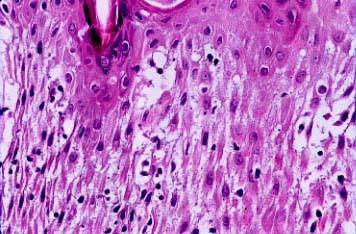

Read MoreCystic_scc = الورم الشائك الخلايا الكيسي OLYMPUS DIGITAL CAMERA OLYMPUS DIGITAL CAMERA